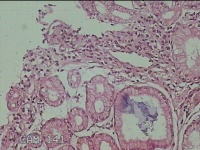

胃角粘膜

性别

男

年龄

29岁

临床诊断

复合性溃疡;慢性胃炎

一般病史

上腹部疼痛1个月余。

标本名称

大体所见

灰白粉红色组织小米大2团。

良性病变。